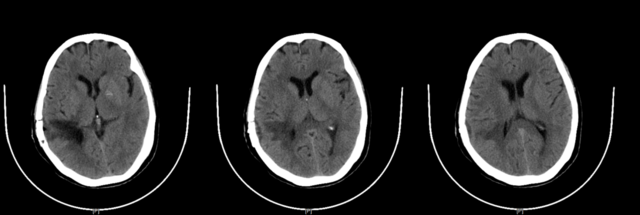

▲患者头颅MR增强

考虑脑膜瘤可能!